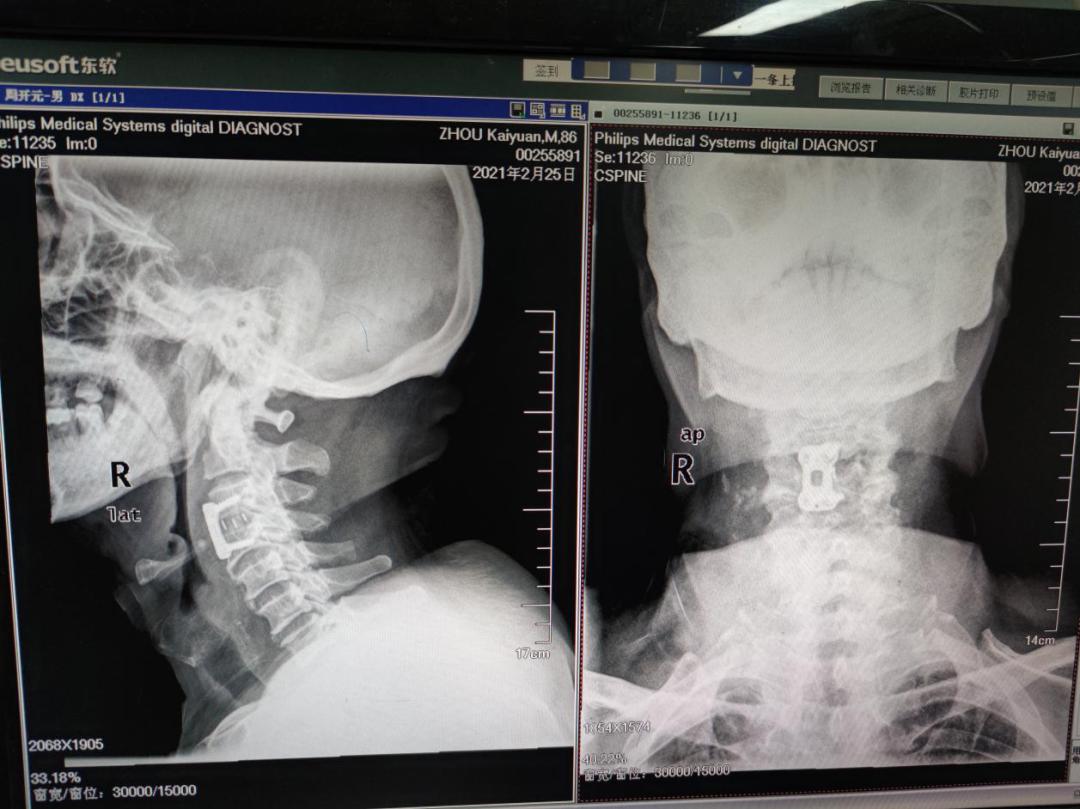

经过吴炳华教授团队诊疗后,发现患者双上肢也存在肌力下降的情况,骨科组织多学科联合会诊讨论后认为,该患者症状来源主要来自C3/4节段的脊髓受压迫造成,随即团队为患者制定精密的手术方案,成功的为患者实施了颈椎前路ACDF手术。术后麻醉苏醒后患肢及感四肢力量明显较术前增强,术后第二天患者就行走自如。

本次手术以最小的创伤,彻底切除了患者严重压迫颈脊髓的骨化韧带及突出的髓核,最大程度地保留了正常的颈椎结构。 吴炳华介绍,由于颈前部解剖结构复杂,术野很小,需要在方寸之间进行切除、松解、融合、内固定等一连串高难度技术操作。特别是颈椎区域存在血管、神经等重要结构,从技术上需要术者具备精准的解剖结构专业知识和丰富的临床手术经验,手术难度系数高。